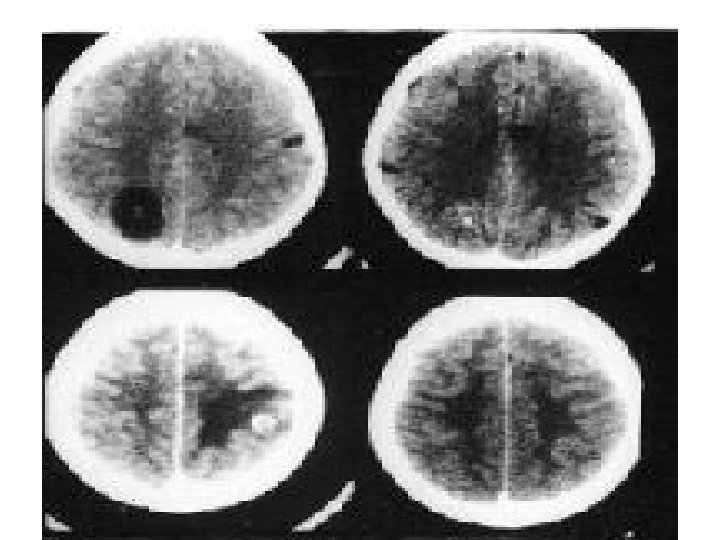

Seizures: Imaging - CT/MRI Has revolutionised the management of epilepsy Indications: focal features on exam, EEG Features of ICT Intractable However, now indicated in every case with unknown cause Not necessary in febrile/absence/BETS/ JME etc. Western studies - 30% abnormal (30 -50% of focal) -only 3% treatable Indian studies: Very high prevalence of granuloma like lesions –recent onset partial seizures in child/young adult 40% abn even after 1 st seizure indicated in every case